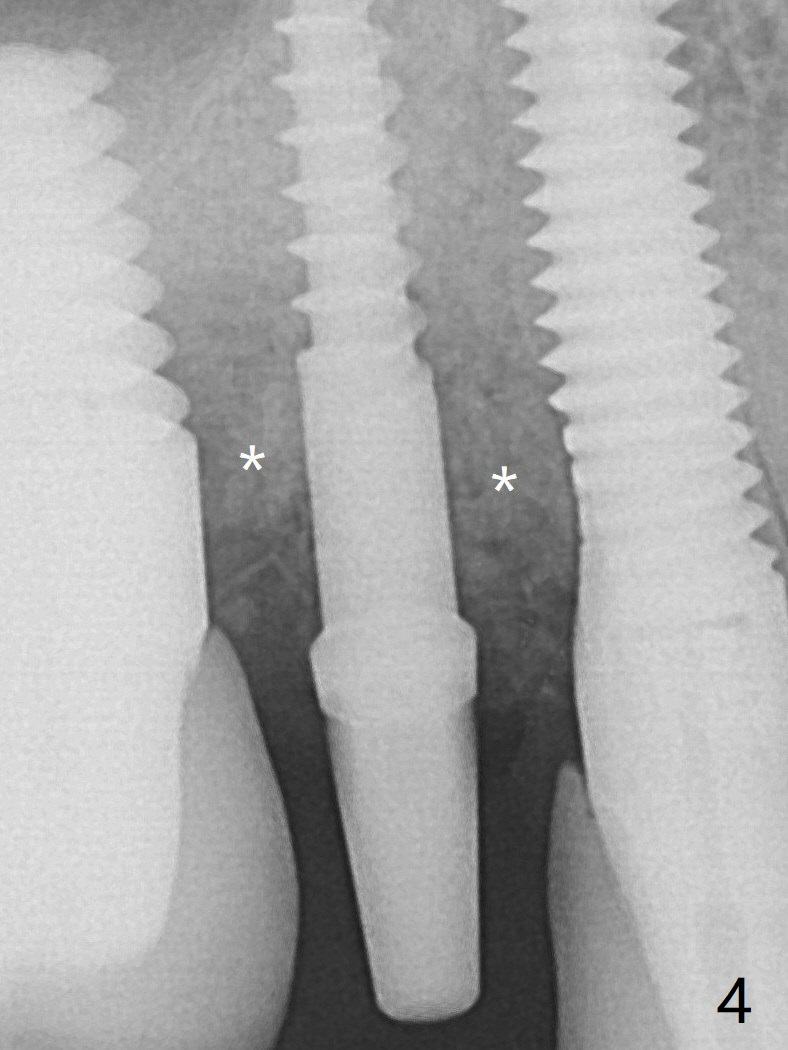

A 2.5x10(4) mm 1-piece implant is placed with <50 Ncm; since the trimmed implant threads at #5 are exposed (Fig.3), Vanilla graft with Osteogen is placed mesial and distal to the new small implant (Fig.4 *). The mesial, coronal implant threads at #3, uncovered by the bone (Fig.3), are not exposed by the incision directly, but the bone graft appears to contact them. There is no bone loss 3.5 months postop (Fig.5,6) or 4 months post cementation (8 months post cementation, Fig.8,9). There is no sign of periimplantitis. The implant remains mobile and symptomatic (chewing pain) 14 months post cementation (Fig.10).